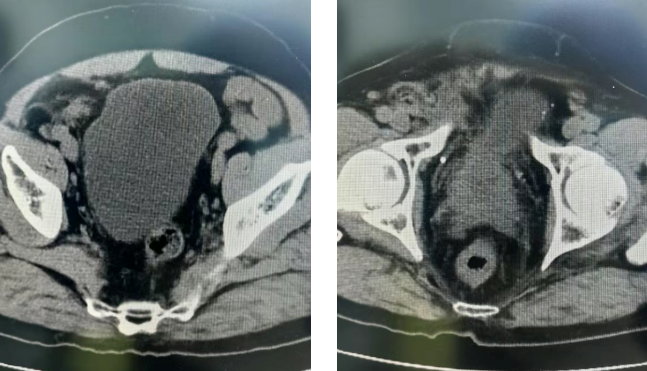

患者为老年男性,2月前查体发现PSA升高,于当地医院确诊前列腺癌。其病情较为复杂:不仅合并高血压、糖尿病、左束支传导阻滞等多种基础病,且三周前刚接受右侧腹股沟疝修补术,膀胱巨大平脐。为求进一步治疗,患者慕名来到山一大一附院泌尿外科王金主任门诊。

面对这一复杂病例,王金主任团队经过详细的讨论评估后,决定采用机器人后入路途径进行切除。在清晰的裸眼3D视野下,术中发现患者的前列腺后方与周围组织明显黏连,界限不清。凭借王金主任多年精湛的手术技巧以及达芬奇机器人超越人手极限的灵活机械臂,顺利将前列腺及肿瘤完整切除,成功保护直肠等重要器官。手术过程顺利,术中出血量少。目前术后患者排尿良好,恢复顺利,无尿失禁发生。